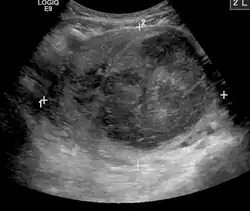

A very large (9 cm or 3.5 in) fibroid of the uterus causing pelvic congestion on US

Chronic pelvic pain

• Veins have one-way valves that help blood flow toward the heart. If the valves are weak or damaged, blood can pool in veins, making them swell. When this happens near the pelvis, it is called pelvic congestion syndrome, which can lead to chronic pain beneath the level of the belly button.

• Pelvic congestion syndrome usually affects women who have previously been pregnant, because the ovarian veins and pelvic veins had widened to accommodate the increased blood flow from the uterus during pregnancy. After the pregnancy, some of these veins remain enlarged and fail to return to their previous size, causing them to weaken and allowing blood to pool.[42]